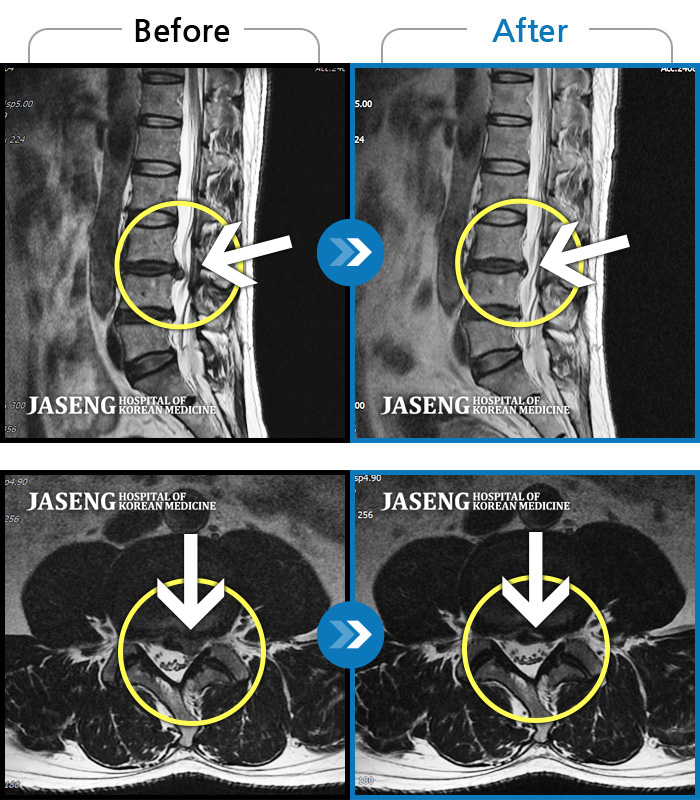

허리통증이 심해서 숙이기 어렵고 차에서 내리기 힘들었습니다.

2021.01.06 ~ 2025.03.10